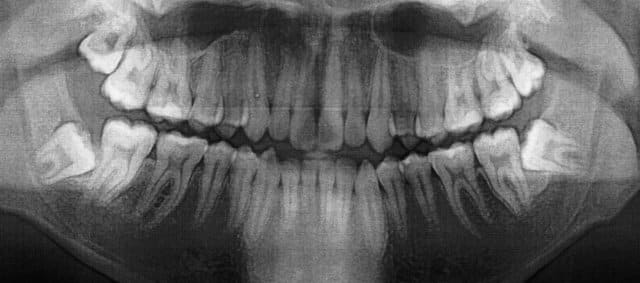

Est ce que vous extrairiez?

J'hésite: proximité du canal dentaire.

ça va, les zones de découpage de la dent sont assez loin. bon courage.

POur l'OTP1, je vois pas bien, donc pas de commentaire.

Pour L'OTP2, tu peux extraire car config parodontale défavorable à long terme, extraire maintenant car apex pas encore formés sinon risque de contact étroit avec canal plus tard. Pas de risque pourle nerf dentaire. tu découpes en autant de fois nécessaire pour tout sortir. si t'es pas sûr, tu prends ton temps et ça sortira.

Canin, es-tu sûr que c'est pas le contraire? Configuration paro défavorable sur le n°1.

Moi perso, le n°2, je le laisserais tranquille, tant que c'est sous-muqueux et asymptomatique.

Osmi,

Non je n'ai pas confondu mais ce que tu dis est vrai. La config paro est pire sur l'OTP1.Je ne vois pas bien l'image du canal mais à priori y'a pas de problème car tu est proche du canal mais au dessus. Tu ne peux odnc pas léser ton nerf sauf si tu forces lors de l'avulsion. C'est pour ça qu'il faut couper au maximum. De plus tu conserves le maximum. Le gros problème, c'est le manque d'accès en rapport avec la branche montante. Il faut que ton patient ouvre bien la bouche et alors y'a pas de problème.

Concernant l'OTP, y'a des chances que la 48 soit vestibulée et donc il doit y avoir quand même de l'os en distal de la 47. Dans ce cas si la gencive est bien kératinisée et saine, pas de poche paro, tu peux effectivement laisser. Mais bon le problème c qu'on peut jamais prévoir l'évolution de ce genre de situation. Le truc c que si la personne semble jeune genre 20 ans environ. Non ???? Si tu enlèves maintenant, la cicatrisation osseuse sera favorable. A 40 ans si il a de la paro, c moins évident et la proximitré nerveuse encore plus délicate à gérer. L'extraction faite maintenant devient donc en quelque sorte prophylactique si tu décides de l'enlever.

Concernant la 38, la config paro est pas top non plus.

Si tu penses pouvoir réaliser une chir sans problème (accès, bon état général, geste sûr) alors je crois qu'il faut enlever.

vu ta pano,le nerf dentaire est assez loinde tes apexs.tu pe demande un scanner pour etre sur.Avec un bon degagement vestibulodistal, une section de la couronne puis des 2racines ca devrai t passer.ne force pas trop qd meme vu la position de ta dent.